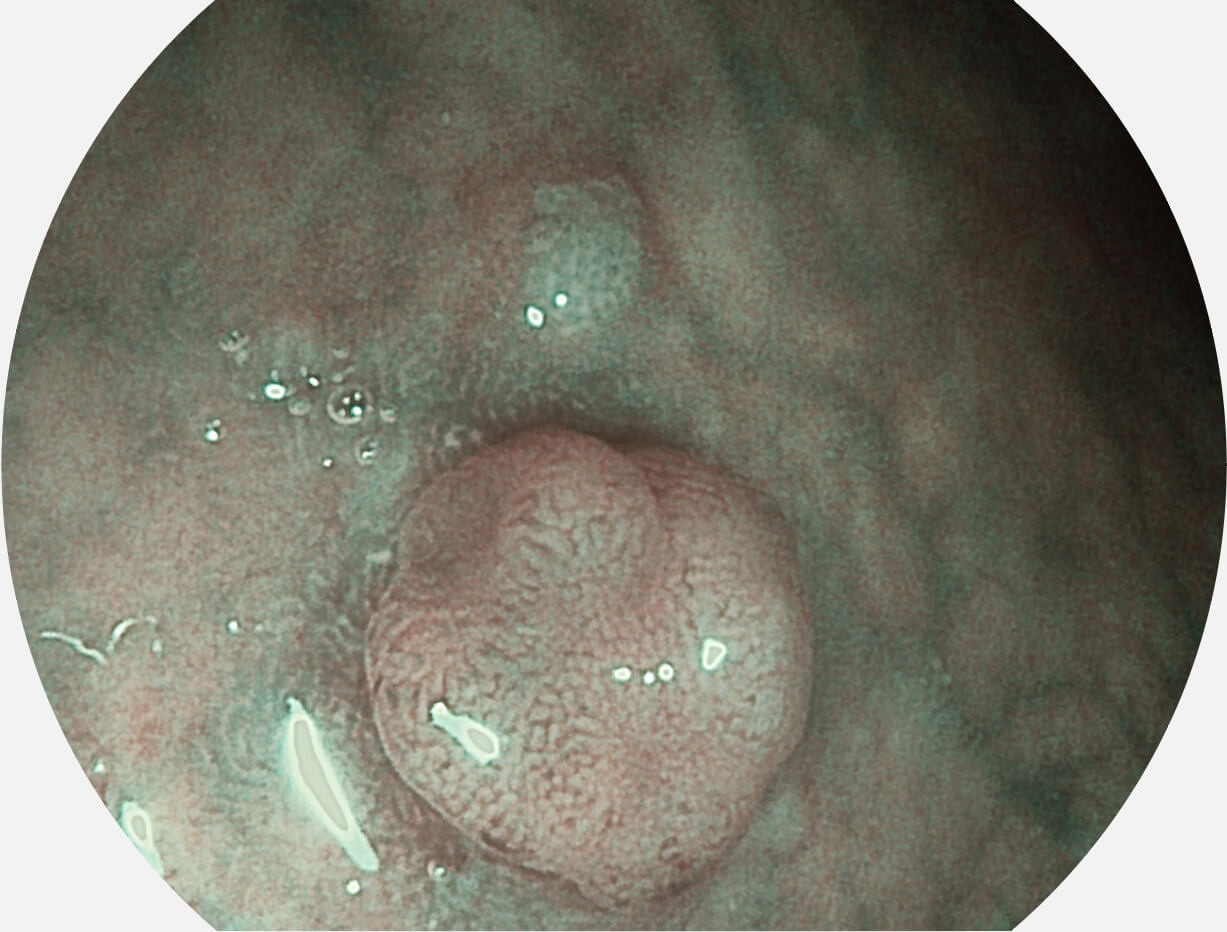

白光图像

SFI图像